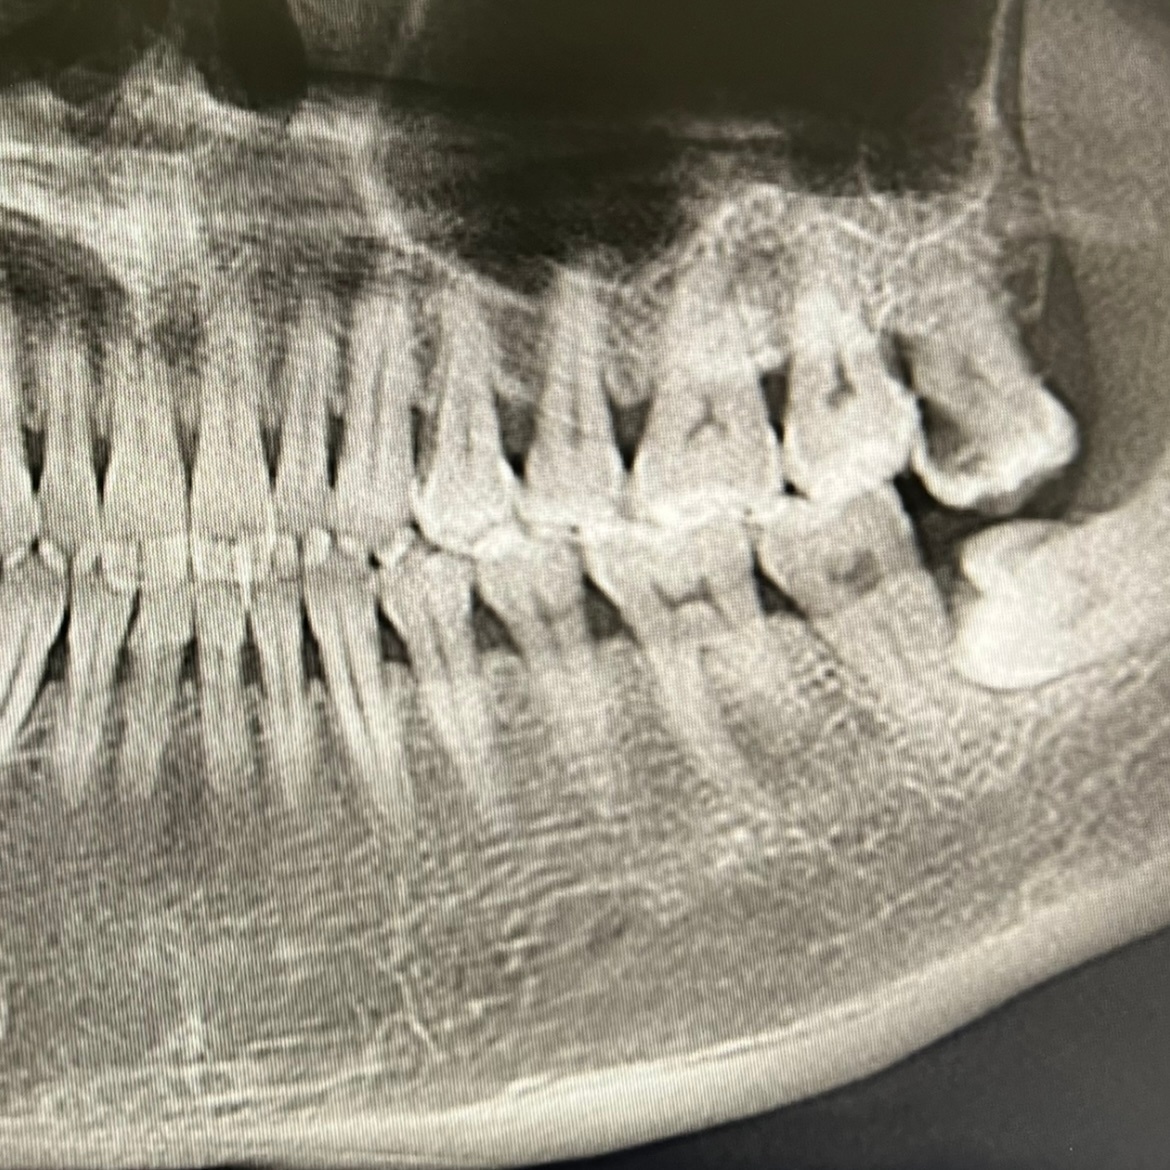

【猝死可能人儿】这几天牙嚼韧的食物感觉不太舒服,付良悄悄给我约了他的牙医去检查(如果不悄悄约,我是不会同意去诊所的),做CT,医生说4颗智齿其中3颗都需要拔掉。来都来了,拔吧。拔牙前测血压,把医生吓到了,192/128mmhg,又测兩次还是这样,医生给自己也测了一下,她的正常。她问要不要叫120去急诊?我说不用了,我出去走走就能好,出去走了一会儿,回诊室医生问要不要再测一下?我拒绝了,彼时,牙科诊所已经给我留下了心理阴影。。平常几乎每天监测血压,大致都是正常范围,今天回家后再测,也正常,又去买了一个血压计,两个同时测结果也大致相同,说明以前测的还算准确,而牙科诊所用的也是同款血压计。。这就是那种白大褂恐惧症或者幽闭恐惧症么?。。不过我也意识到自己可能是那种有猝死危险的人,却也没什么好怕的,猝死刚好是我最喜欢的死法。

医生说我牙挺好,

清洁做得好,

没有龋齿,

牙质坚硬。

我自己的感觉可能是上火了,

不必急着拔牙,

最近注意清淡饮食

观察一下再说。

血压太高没拔成牙,

回家后血压也不高了,

牙也不怎么难受了,